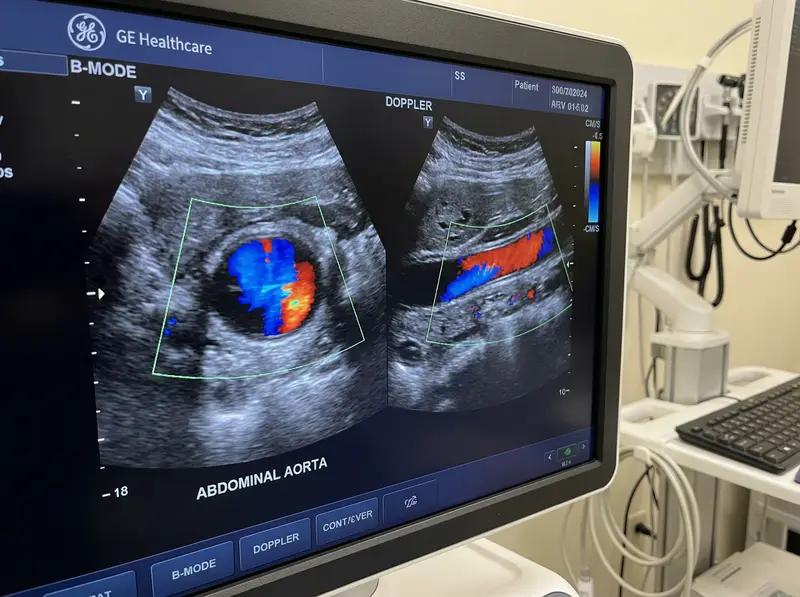

Ultrasound-scan is the gold-standard imaging method for AAA detection and surveillance. The scan is painless, uses no radiation, and produces real-time images of the aorta and its branches. At Sonoworld, the examination is performed by an HCPC-registered vascular sonographer using a GE Voluson system, with a written report issued within 24 hours.

The examination evaluates the aorta and iliac vessels using greyscale imaging and colour Doppler. The table below summarises the structures assessed and the conditions identified.

You lie on the examination couch and expose your abdomen. Warm ultrasound gel is applied and the probe is moved across the skin. The aorta is measured in both transverse and longitudinal planes.

Doppler colour flow is applied to assess blood flow direction and velocity within the aorta and iliac vessels. This identifies turbulence, thrombus, and areas of stenosis.